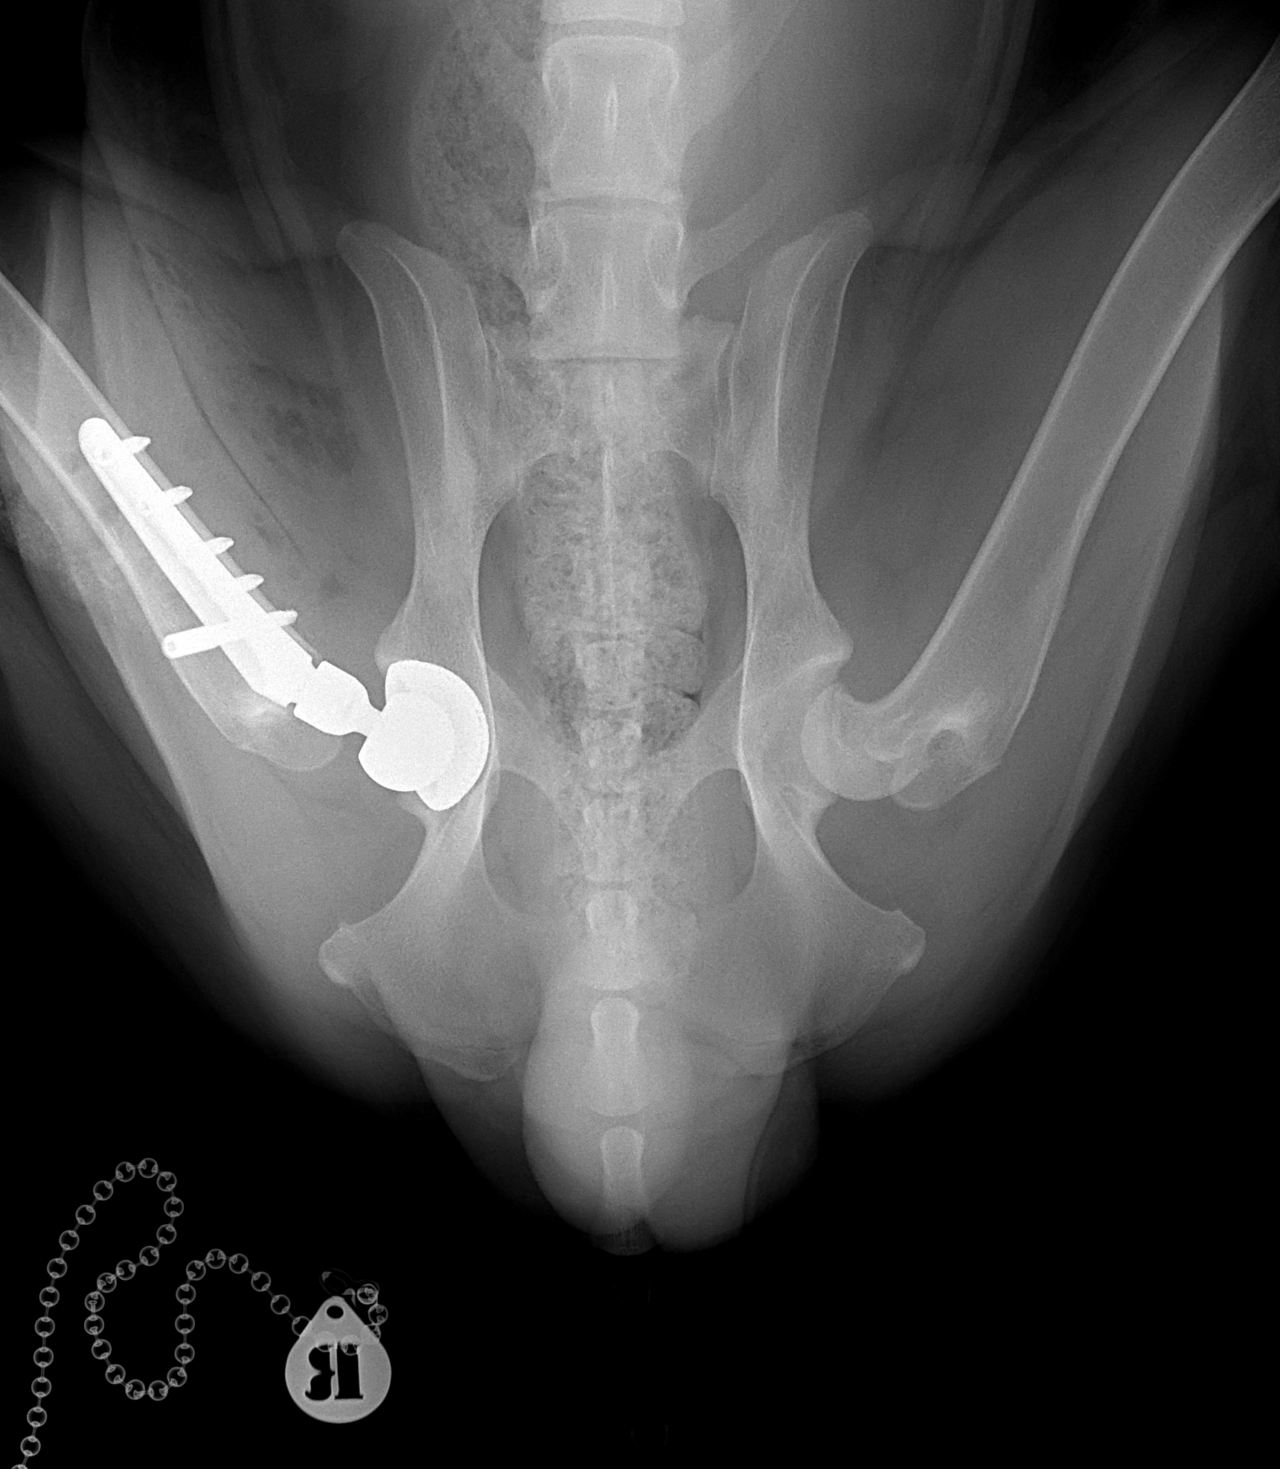

THR #24 大型犬の股関節形成不全のパピーに最も除痛効果と機能回復が期待できるトータル・ヒップ・リプレイスメントで対応しました。しばらくは安静が必要です。 症例カテゴリー 放射線治療整形外科軟部組織外科脳神経外科内科腫瘍外科救急・集中治療リハビリテーション科腫瘍内科内視鏡科脳神経科呼吸器外科中医・漢方猫の腎移植循環器科